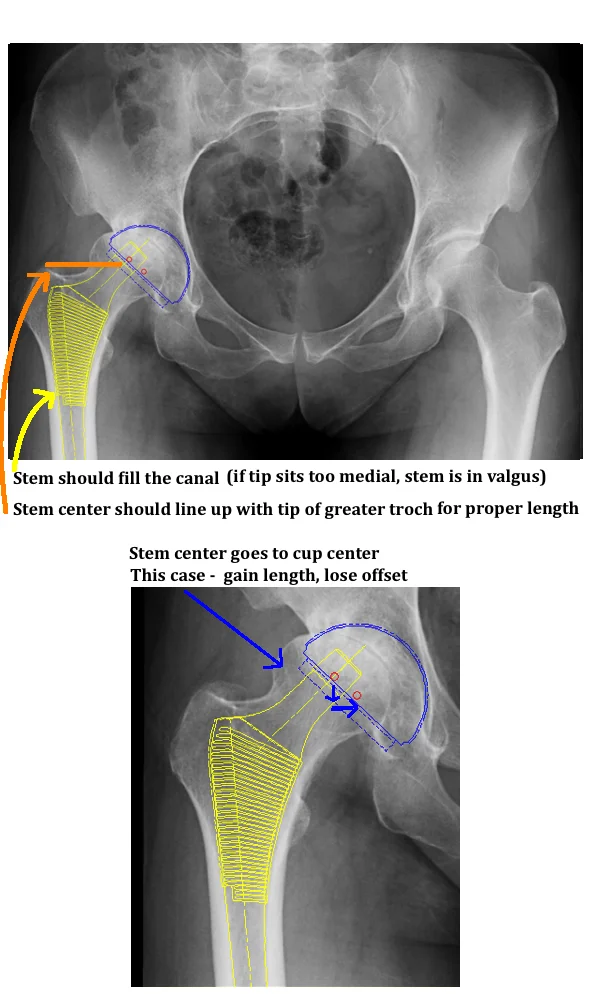

TEMPLATING THA — Hip & Knee Book - A fundamental step when templating a total hip arthroplasty is to identify the true magnification of the radiographs. Explore the benefits of joint templating for patients undergoing orthopedic surgery. Joints® plan is the simple, fast and accurate implant templating solution that allows orthopedic implant sales representatives to automatically receive studies from collaborating practices,. This document discusses the concept and methodology. You should also read this: Real Estate Business Card Templates

Digital templating of knee arthroplasty; lateral view with reference - Digital software templating has been adopted. A fundamental step when templating a total hip arthroplasty is to identify the true magnification of the radiographs. People with severe hip joint. It begins by defining templating as a radiographic planning process. Preoperative templating helps guide the selection of implants and. You should also read this: Google Doc Birthday Template